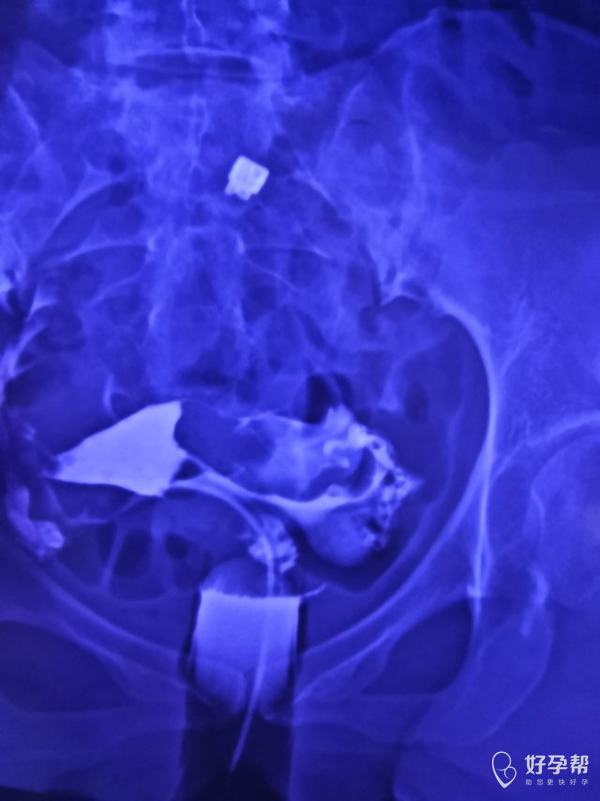

输卵管通而不畅伞端粘连试管三次未成后续是试管